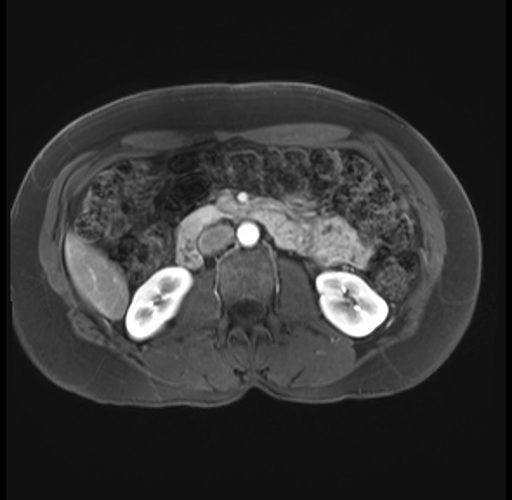

Imaging Analysis

Look through the patient's CT scan to identify any areas of concern for the necessary procedure.

Based on your CT findings, which issue(s) are present and would give reason for "planned slowing down moment(s)" in this case?